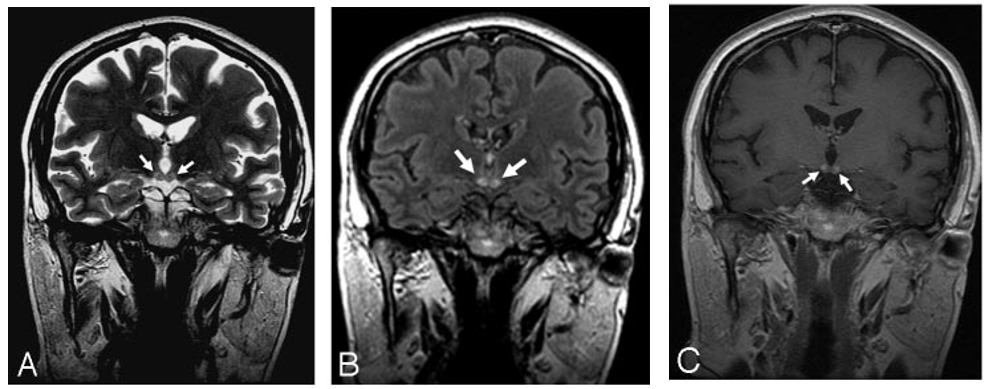

Marchiafava-Bignami病

简称MBD,是一种罕见的以胼胝体脱髓鞘和坏死为主要病理特征的慢性酒精中毒相关性疾病。这种病的临床表现无特异性,急性起病者可出现严重的意识障碍和认知损害,常危及生命;慢性起病者主要表现为进行性痴呆。

急性期典型影像学表现为“三明治征”,即:矢状位上的病变主要位于胼胝体中层,上层和下层正常。以胼胝体全段受累更为常见。急性期后,胼胝体异常信号逐渐消退。

慢性期表现为胼胝体萎缩,伴局灶性长T1、T2信号,可能反映了进行性脱髓鞘、局灶性坏死和囊变。如果病变出现在胼胝体外,则以皮质下白质最为多见。

颅脑MRI矢状位FLAIR示胼胝体压部高信号(A)

DTI示同一部位胼胝体横向纤维受损(B)

DWI和ADC示胼胝体压部细胞毒性水肿(C、D)

颅脑MRI、DWI示:

双侧大脑半球皮层下白质、

胼胝体、双侧小脑中脚高信号